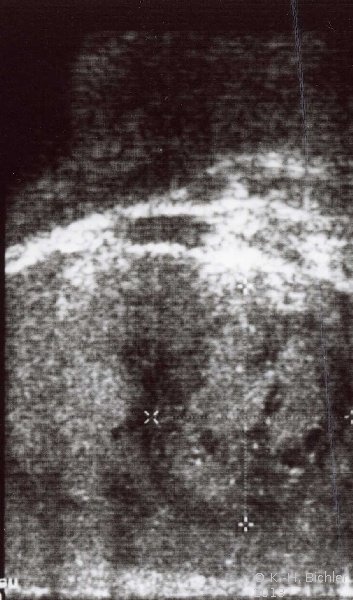

Der Patient kam wegen Schmerzen und Schwellung im rechten Hoden zum niedergelassenen Urologen. Die Untersuchung ergab palpatorisch Verdacht auf Tumor im rechten Hoden. Sonographisch fand sich ein umschriebenes, tumorverdächtiges Areal (

s. Abbildung 10a). Die Tumormarker waren erhöht: AFP 390 ng/ml und hCG 12,3 mIU/ml (Abbildung 9).

Die Hodenfreilegung ergab im Schnellschnitt ein embryonales Karzinom mit Teratomanteilen vom intermediären Typ und Dottersacktumor. Das Organpräparat zeigte auf der Schnittfläche einen umschriebenen Tumor von heterogener Struktur: Einblutungen, zystische Areale, gallertige Formationen (Abbildung 10).